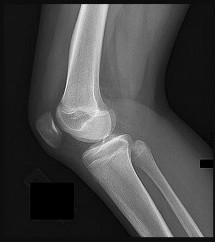

Figures 5a and 5b are the radiographs of a 74-year-old man with poorly differentiated squamous cell carcinoma of the lung. He has had an uneventful recovery after undergoing a wedge resection of his left upper lobe 6 months ago. He is experiencing left lateral knee pain, and a whole-body positron emission tomography/CT scan shows no avid area other than the lateral left distal femur. This patient has needed to use a wheelchair for 3 weeks because of his pain. You discuss these treatment options: aggressive curettage, local adjuvant treatment, cementation, and prophylactic fixation vs distal femoral resection and megaprosthesis total knee arthroplasty reconstruction. You should tell him that

Distal femoral megaprosthetic reconstruction after tumor resection is a reliable oncologic procedure, but 5-year implant survival is as low as 74% with an approximate 8% deep infection rate. The amputation rate is as high as 8% because of infection or recurrence, and there is an overall 18% revision rate. More than 10% of distal femoral megaprosthetic reconstructions are performed to address metastatic disease.

Fixation failure and infection may occur with either procedure. Radiation may not be recommended after a megaprosthesis reconstruction unless margins are not free of tumor. Either operation may be equally successful in returning patients to functional activities. Overall disease-free survival is related to the aggressiveness of the tumor and not the type of reconstruction performed.